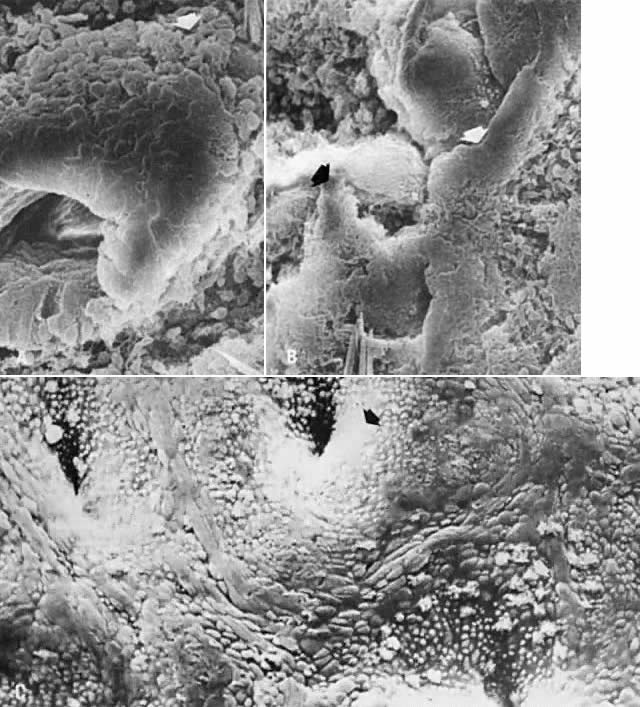

Fig. 5. Scanning electron microscopy of regenerative endometrium. A. On cycle day 3, gland stumps of residual basal glands have epithelial extensions ( arrow) onto denuded stroma (×380). B. Cycle day 4 is dominated by anastomoses of epithelial membranes ( arrows) from adjacent basal gland openings (×230). C. By cycle day 5, the surface is fully regenerated. Note concentration of ciliated cells ( arrow) around gland openings (×300).

Starting on day 2 and for the subsequent 2 days, proliferation of the basal gland epithelium begins in the areas of denudation.6 The surface of the endometrium is re-epithelialized as the residual glandular epithelium spreads over the denuded surface (see Fig. 5A). Another source of resurfacing epithelium is the surface epithelium of peripheral regions of the endometrial cavity, such as the lower uterine segment and peritubal ostia, which remain intact during the menstrual period.6 The subsequent development of interanastomoses between converging epithelial proliferations (Fig. 5B) leads ultimately to complete reconstruction of a new surface epithelium by cycle day 5 (Fig. 5C). Complete re-epithelialization of the surface coincides with cessation of bleeding.